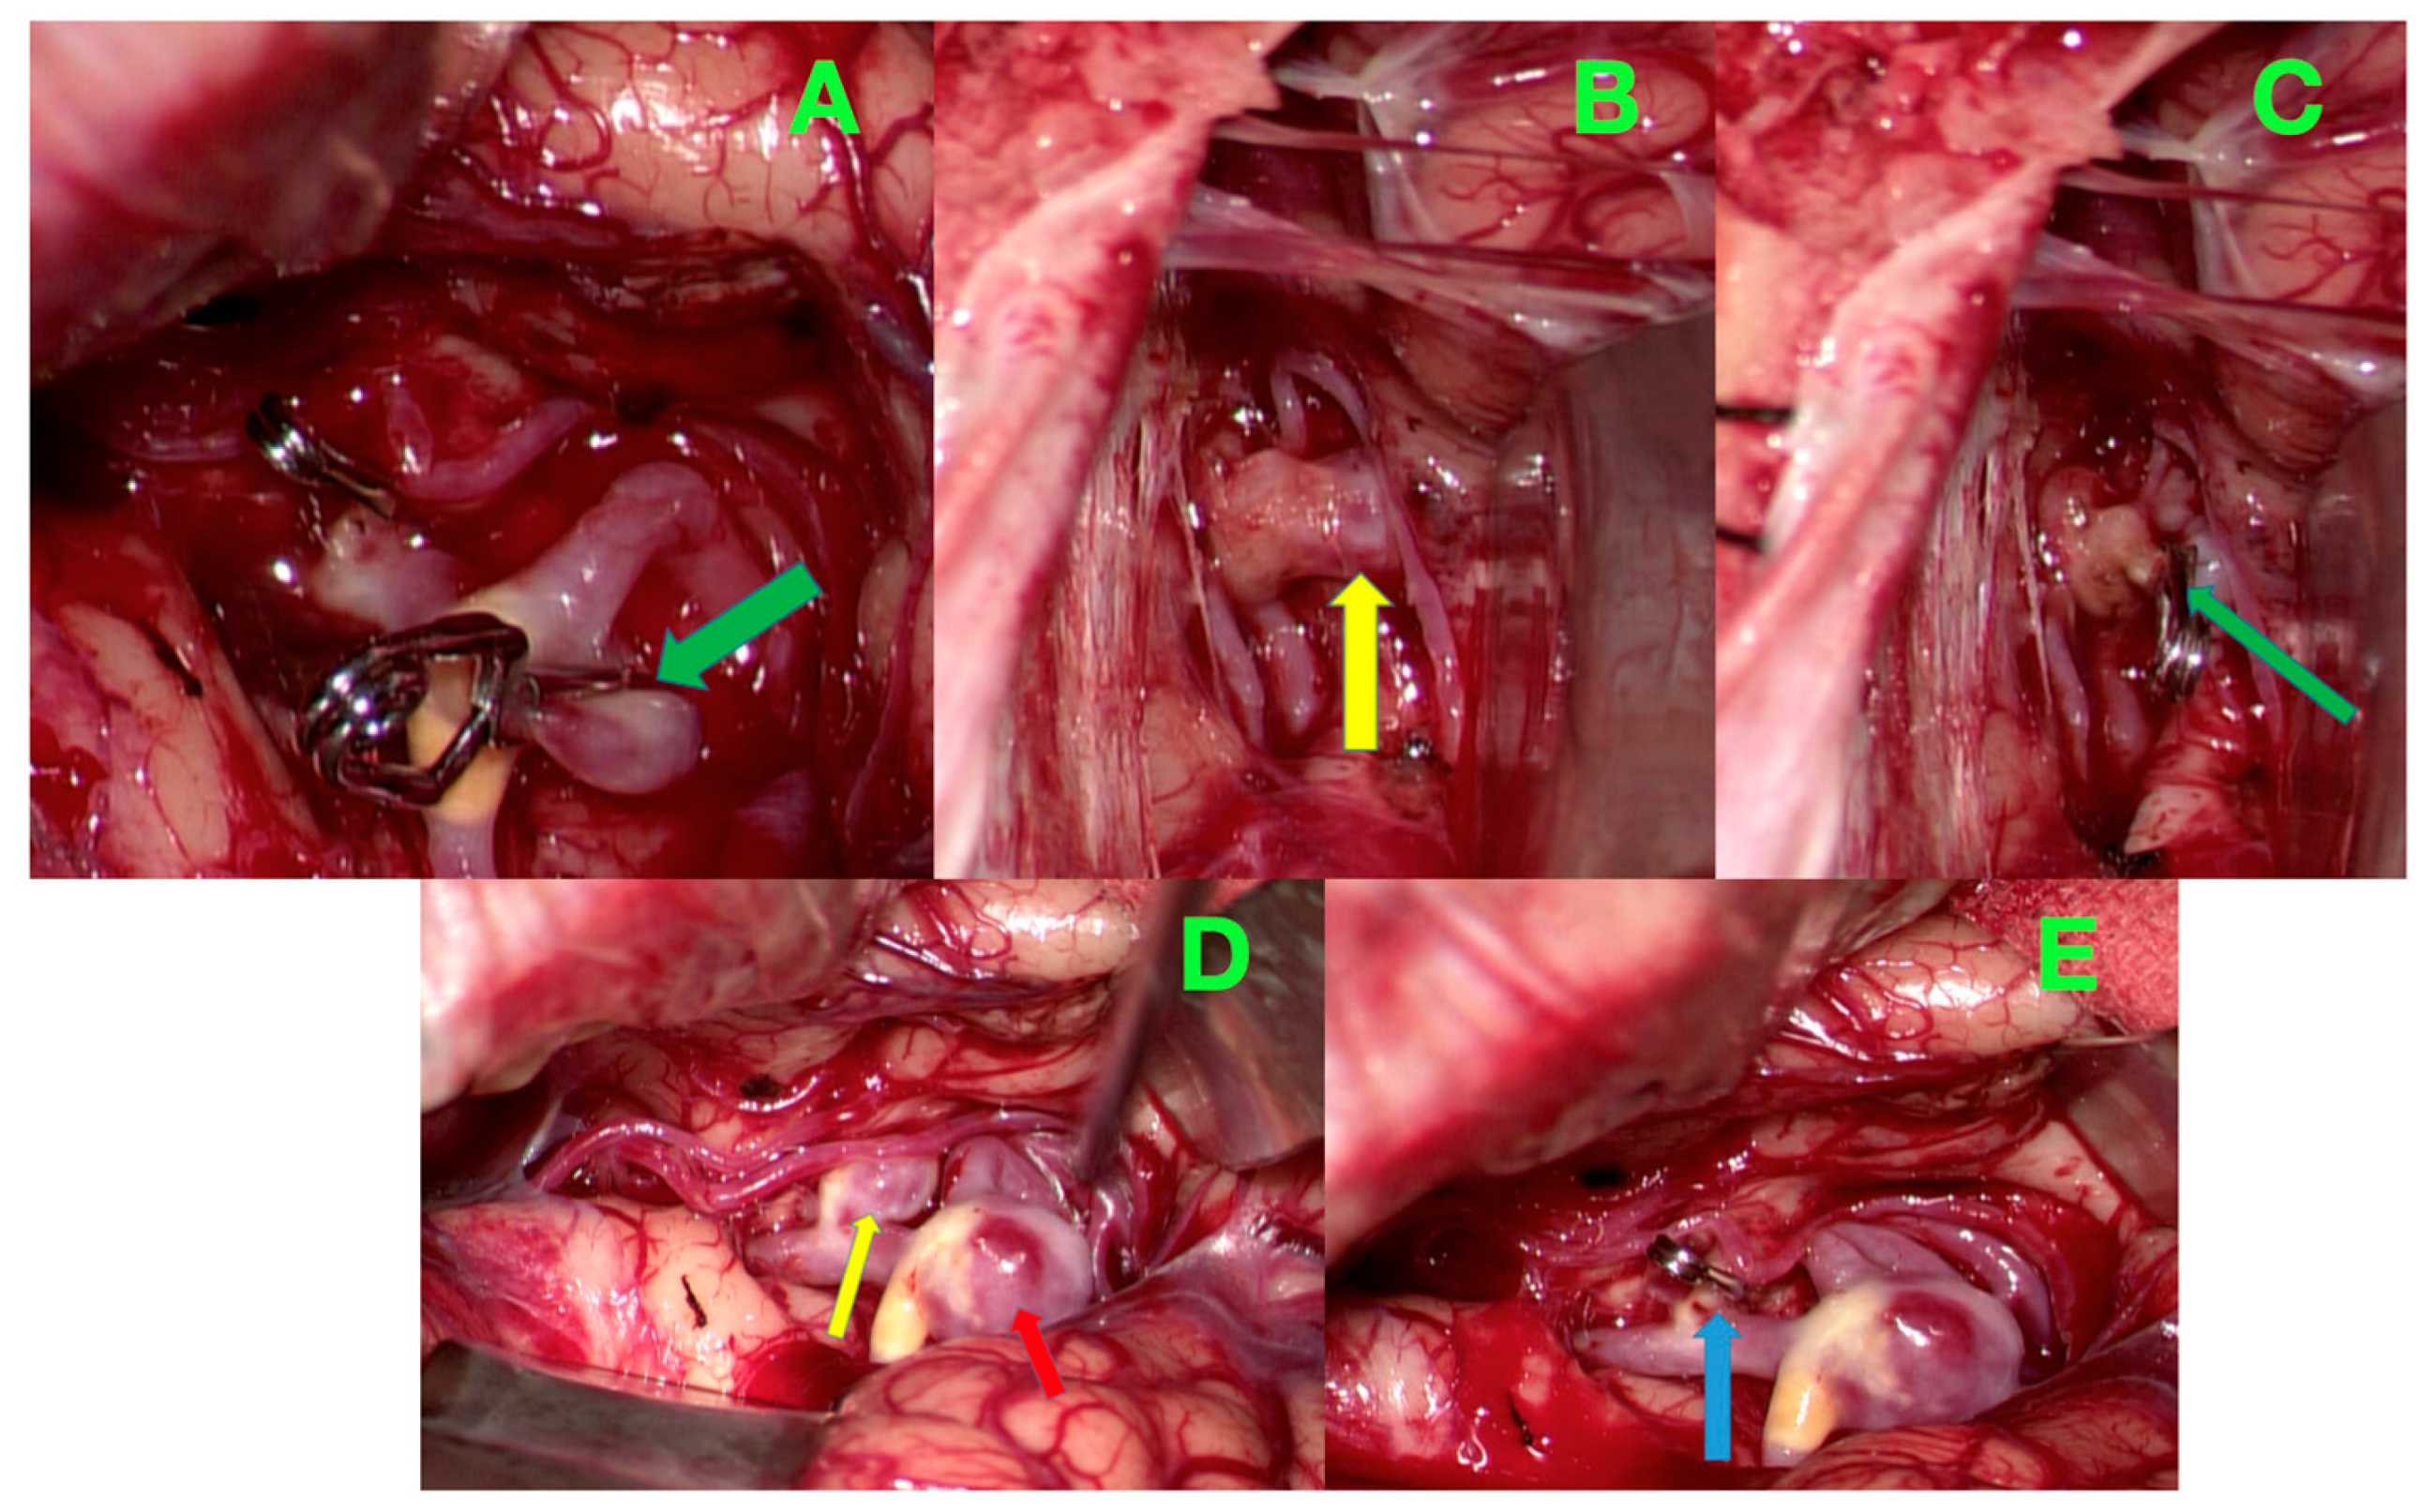

2. Case Presentation